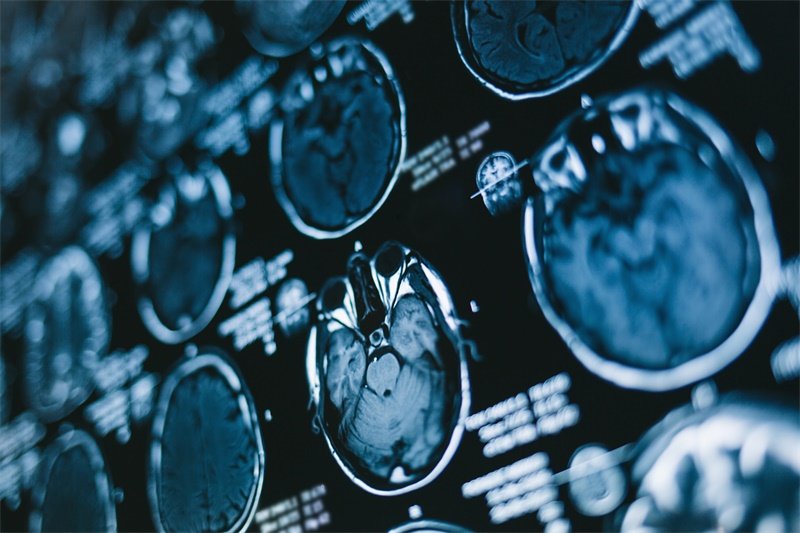

随着医学影像技术的不断进步,CT (计算机断层扫描) 在对颅底和颈静脉孔的诊断中发挥了至关重要的作用。许多患者及其家属在进行相关检查后,往往会对CT结果中的“占位”现象感到疑惑。

CT (计算机断层扫描) 是一种广泛使用的医学影像学工具。它通过X射线拍摄多个角度的图像,并利用计算机将这些图像合成,形成详细的内部结构图。

CT检查可以提供该区域的高分辨率图像,帮助医生判断是否有肿块、肿瘤、感染或者其他病变。通过CT影像,可以清晰地看到血管和邻近结构,为后续的诊断和治疗提供重要依据。

CT检查的结果会被仔细分析,医生会基于图像特征进行初步判断。如果发现异常,可能会建议进行进一步检查,比如MRI或组织活检。

CT影像的分析通常由专业的放射科医师来进行。他们会根据影像学特征,如占位的大小、形状、边界、密度等来进行评估,并将结果报告给主治医生。